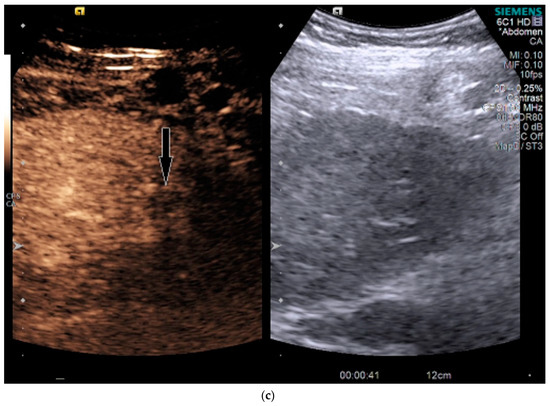

Figure 3.

Patient 2 ultrasound images, with liver lesion denoted by black arrow: (a) grayscale images showing the hypoechoic lesion. Post contrast administration ultrasound in arterial phase (b) and early washout (c) of the lesion, LI-RADS M.

On grayscale US, a subtle 1.2 cm hypoechoic focal area was identified on a background of echogenic, heterogeneous liver echotexture (Figure 3). This area was targeted with contrast, which showed avid arterial-phase enhancement, and rapid, but mild washout (Figure 3). This was also designated LI-RADS M due to the early washout. CT was performed to confirm the finding and initially, the lesion was not identified by the radiologist, despite a diagnostic late arterial phase. On closer inspection with the US finding in mind, subtle enhancement and washout on the CT was seen and considered LI-RADS 4 (Figure 4), and due to this designation and its small size, a shorter interval follow-up was performed at 3 months rather than 6 months.